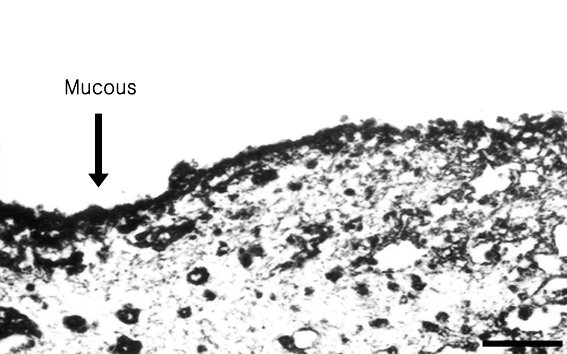

Figure 4. Transmission electron microscopy

Transmission electron micrographs of human corneas treated with 0.01% BAC solution. A: The negative control cornea (no BAC) showed no mucous layer. B: The positive control cornea fixed with CPC showed a well defined mucous layer. C: Cornea treated with BAC solution for 5 min showed a thin trace of mucous layer on the surface. D: Corneas treated with BAC solution for 15 min showed a thinned mucous layer. E: Corneas treated with BAC solution for 60 min had a near total loss of the mucous layer. The mucous present was mostly seen clumped near the epthelium, but no longer attached to it. Scale bars represent 1 μm.